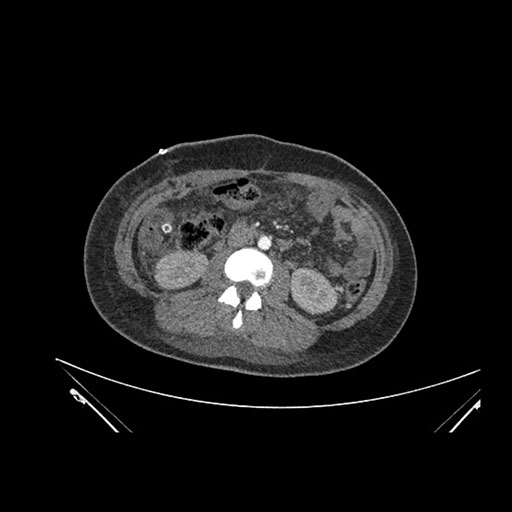

Axial Arterial

Axial Venous